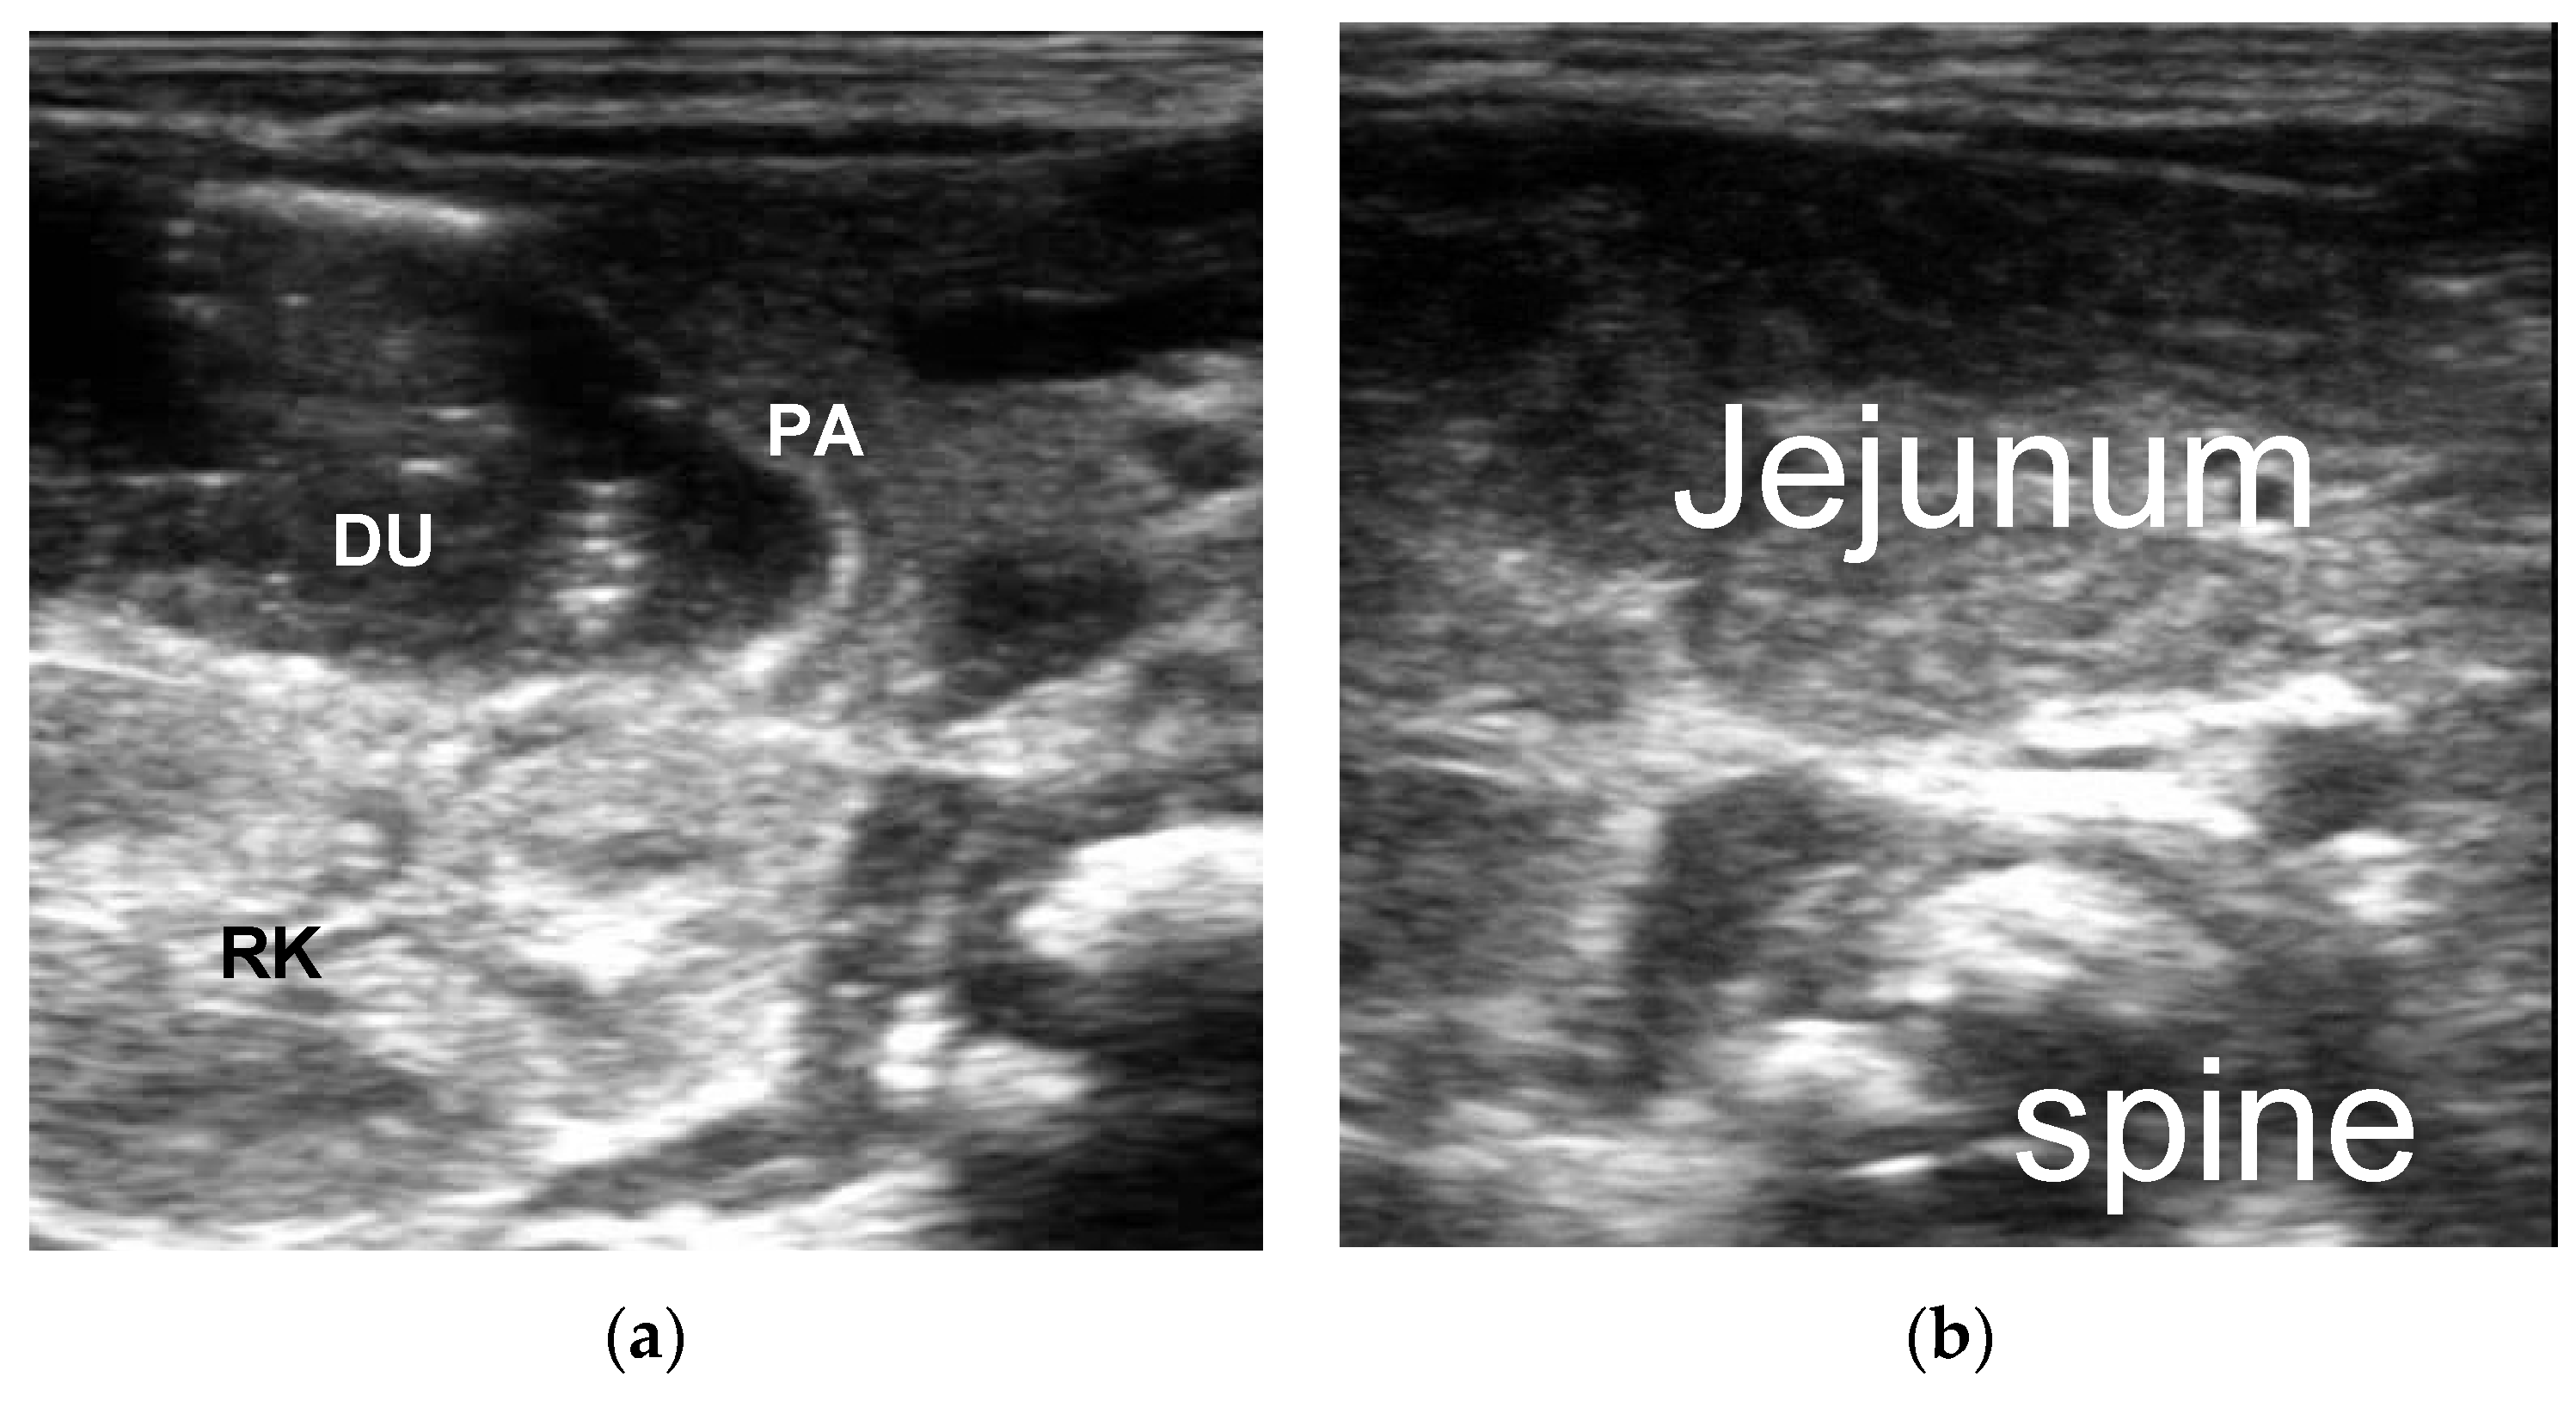

3.2.2. The Corresponding Ultrasound Findings of Diseases Leading to Neonatal Ileus